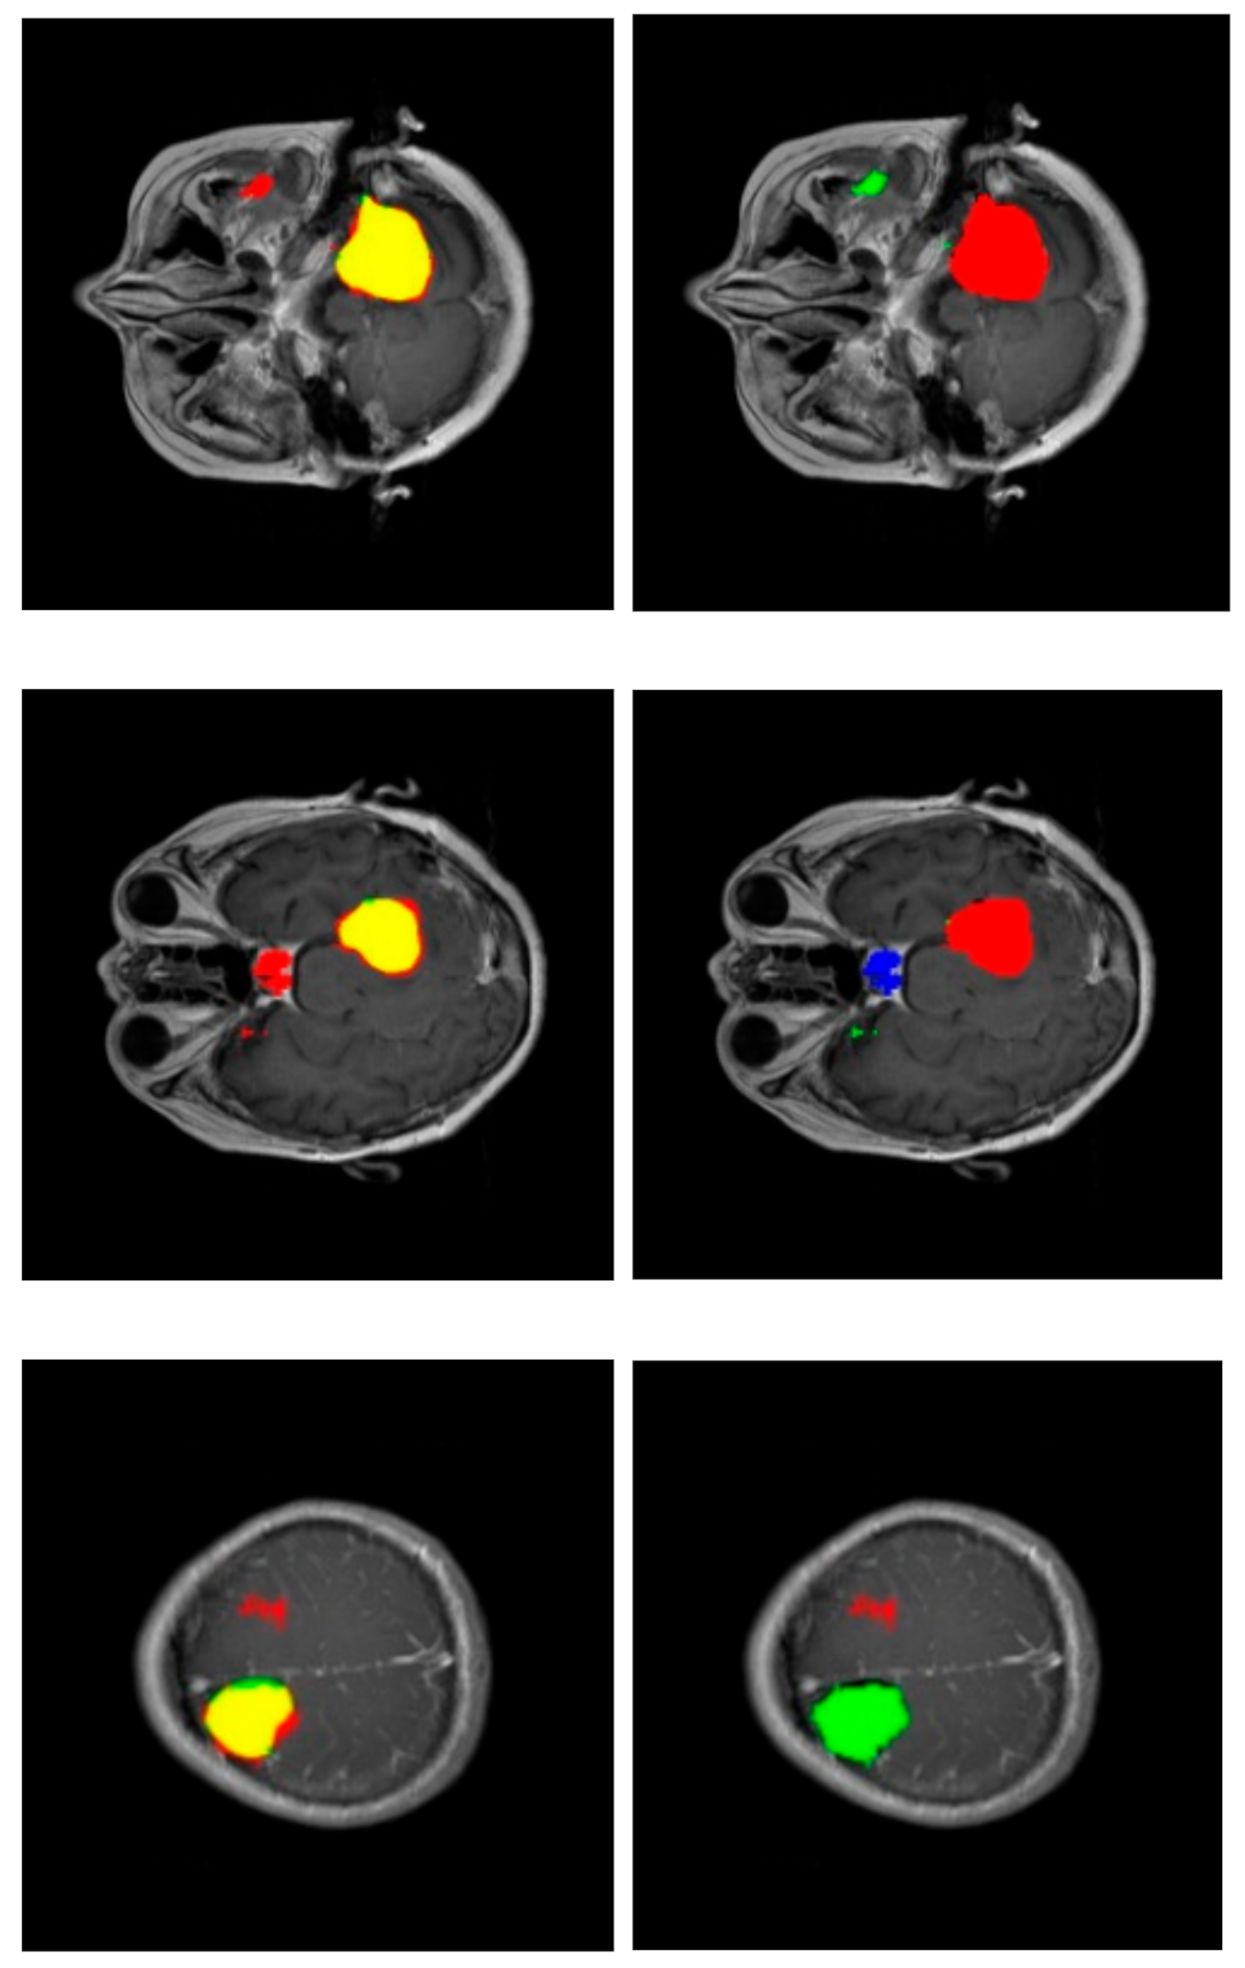

Figure 4 shows the performance of our method for three slices. Figure 4—left—corresponds to a slice with a meningioma tumor, Figure 4—center—shows a glioma tumor, and Figure 4—right—a pituitary tumor. The images show the tumor segmentation obtained, . To mark them with different colors, color images were generated where the predicted tumor region is filled with red color, the ground truth tumor region, , is colored green, and the intersection of those two regions appears in yellow.

Figure 4.

Examples of results of the proposed method for three slices corresponding to meningioma, glioma, and pituitary tumors, respectively. The images show the tumor segmentation: The region detected is shown in red while the ground truth region is shown in green. As a result, the intersection region is shown in yellow.

Figure 6 shows some segmentations with misclassified areas; in the example of the upper row, the greater part of the detected tumor is correctly labeled (red area in the right column), resulting in a very correct segmentation (yellow area in the left column). However, there is a region detected in the non-cerebral area wrongly labeled as glioma tumor (green area in the right column). This example shows the added complexity inherent to this dataset due to the fact that it includes non-cerebral areas that can generate false positives. This complexity also manifests itself in the example of the middle row. Similarly, the segmentation is relatively correct (yellow region in the left column), but there is a misclassified area labeled as a pituitary tumor (blue region in the right column) located in the sphenoidal sinuses area, which is where pituitary tumors appear. The physical structure of the sphenoidal sinuses led to confusion to our model. The third example (lower row) shows a confusion between a real glioma (green region in the right column) and a wrongly predicted meningioma region (red area in the left column).

Figure 6.

Confusion in segmentation. Color-generated images for proper visualization of regions. Upper row corresponds to a meningioma tumor, middle row to a meningioma tumor, and lower row to a glioma tumor. Right column shows the predicted tumor tags (red: meningioma, green: glioma, blue: pituitary tumor). Left column shows segmentations (red: predicted, green: ground truth and, as a result, the intersection is shown in yellow).